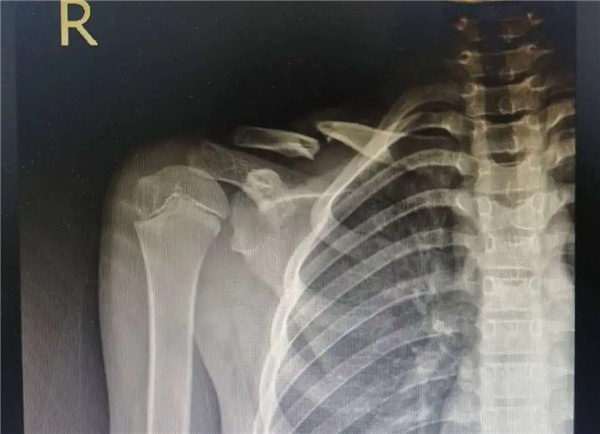

復(fù)位前

經(jīng)拍片顯示,洋洋右鎖骨中遠(yuǎn)段骨折。查體時(shí),洋洋右肩部腫脹,有壓痛感,右肩關(guān)節(jié)上舉、外展活動(dòng)受限,建議其入院并接受手術(shù)治療。洋洋媽媽當(dāng)即辦理了入院手續(xù)。

6月3日,在征得家屬同意,洋洋的身體符合手術(shù)指征后,洋洋接受了右鎖骨骨折切開(kāi)復(fù)位內(nèi)固定術(shù),手術(shù)由應(yīng)文世主任主刀。術(shù)中可見(jiàn)右鎖骨呈粉碎性骨折,骨折端移位明顯。一個(gè)小時(shí)后,手術(shù)順利結(jié)束。術(shù)后,洋洋恢復(fù)良好,6月9日順利出院。一個(gè)月后,在來(lái)復(fù)查時(shí),洋洋的媽媽帶來(lái)了一面錦旗送予應(yīng)文世主任及手外科周小君副主任,以感謝他們的高超技術(shù)及優(yōu)質(zhì)服務(wù)。